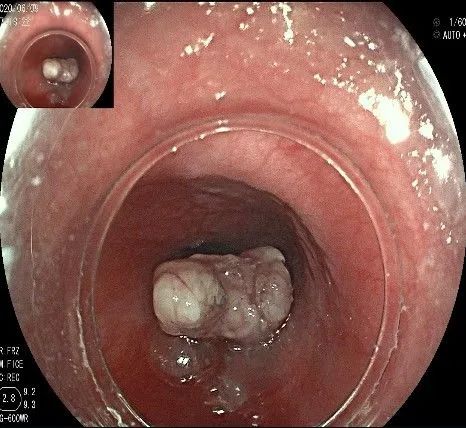

正镜观察,瘤体就在贲门部齿状线的下方。

再次进镜观察,齿状线炎性息肉的地方,用圈套器圈套后通电切除。

瘤子切除后,在粘膜切开的地方,固有肌层的纵形肌处形成一个开口。

倒镜观察,隆起已经消失。